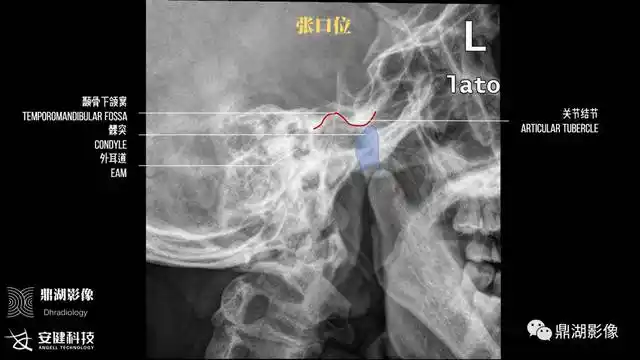

x线高清图谱精致颞下颌关节解剖